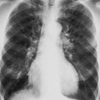

73

Dx

EPOC

74